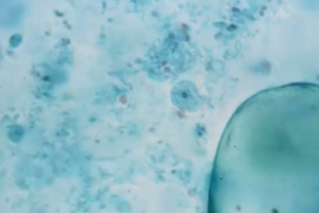

What is the species in this photo and WHY?

Entamoeba histolytica/Dispar CYST. Cysts to not eat RBCs and it is very rounded with 4 nuclei